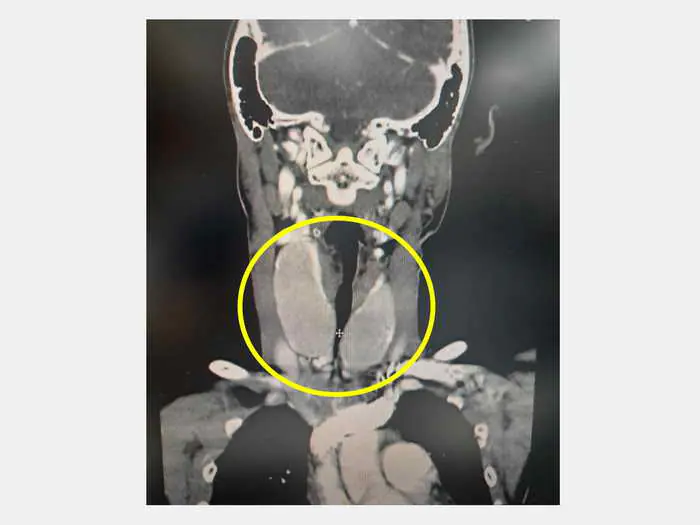

圖一:巫奕儒主任指出,電腦斷層可見病患呼吸道氣管受到壓迫只剩一點點縫隙。

圖二:電腦斷層可見病患呼吸道氣管受到壓迫只剩一點點縫隙(黃圈內下方十字處)。